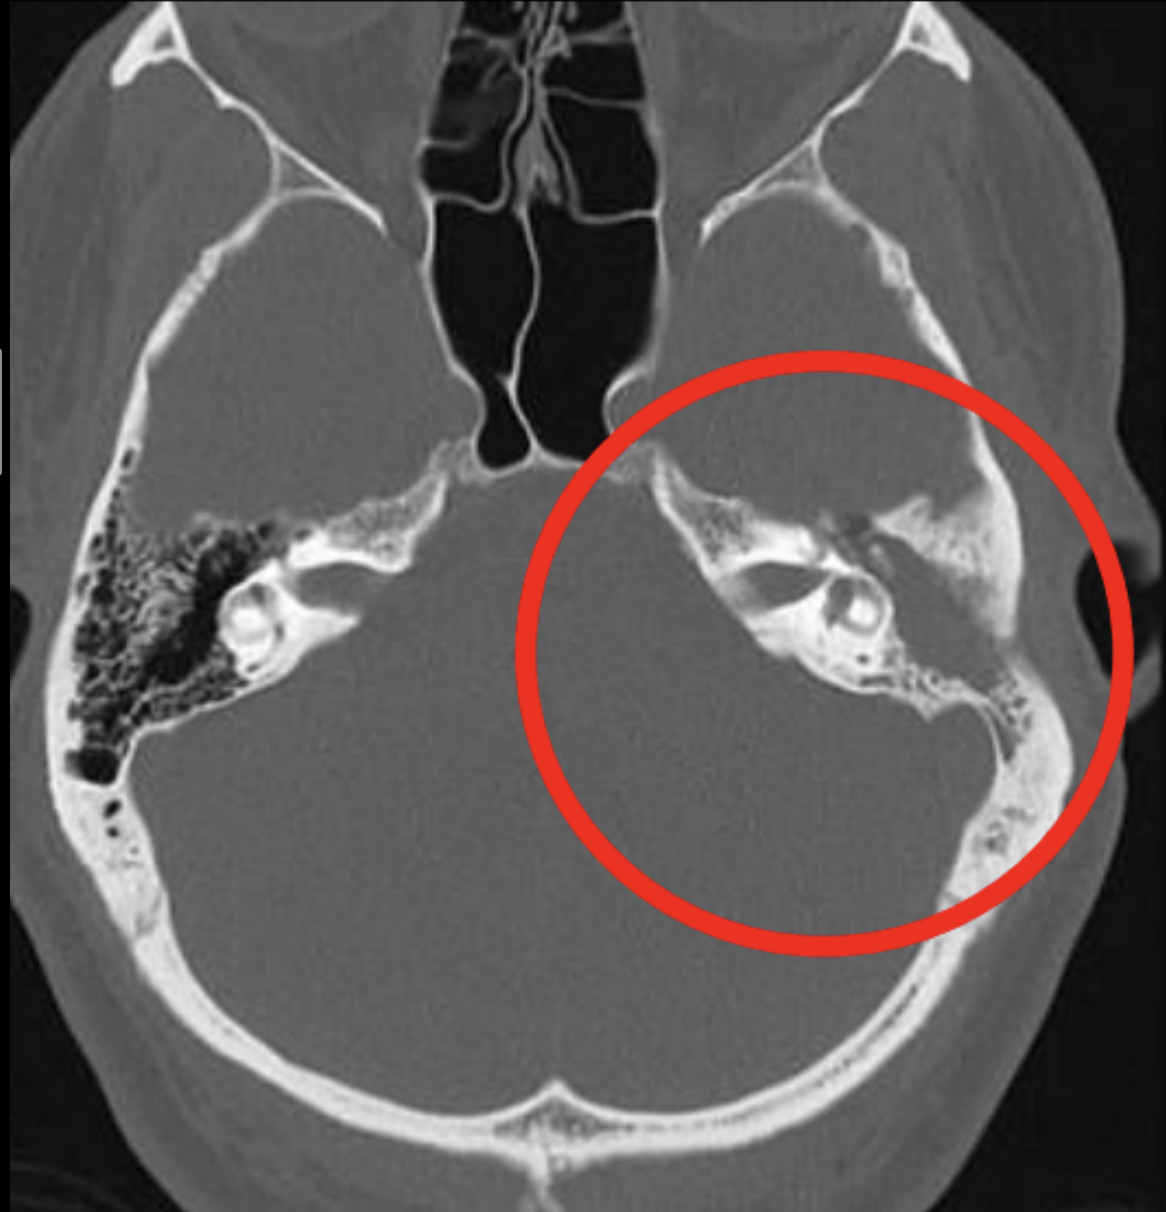

16

Q

Sospecha diagnóstica

17